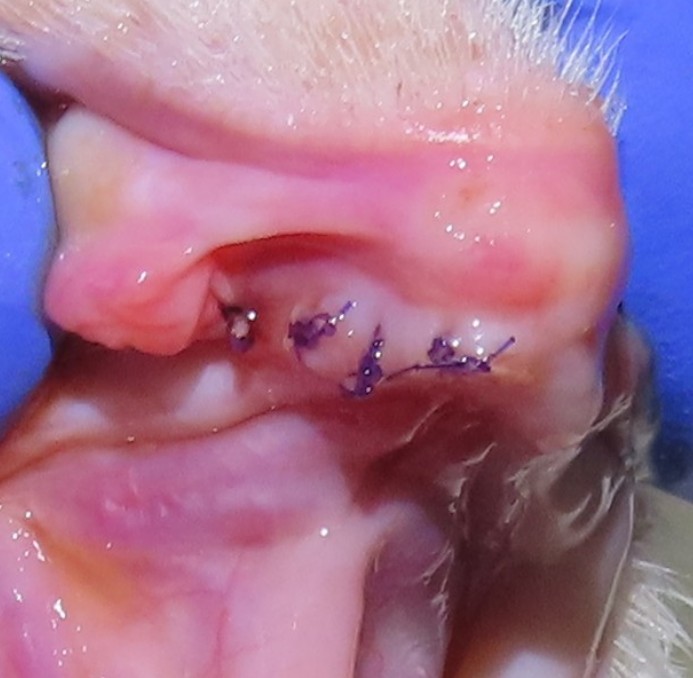

검진 과정에서 송곳니 주변에 치주염 소견이 확인되어 보호자분과 충분한 상담을 진행한 후, 향후 염증의 재발과 통증을 예방하기 위한 예방적 발치까지 함께 진행했습니다.

이번 아이의 경우도 종합검진 중 치아 문제를 새롭게 발견한 것이 아니라, 과거 본원에서 발치 치료를 받은 이력이 있었기 때문에 원장님이 해당 내역을 숙지하고 있었고, 보호자와 충분히 상담한 뒤 송곳니 치주염에 대한 예방적 발치를 결정한 케이스였습니다.

시급히 제거가 필요한 단계는 아니었지만, 향후 염증 악화 가능성과 관리 부담을 함께 고려하여 진행된 치료였습니다.

이번 사례 역시 보호자분과 천천히 이야기 나누며 예방적 발치로 진행되었고, 이후 회복도 안정적으로 이어졌습니다. 병원은 앞으로도 단순한 수치나 검사 결과만이 아니라 각 보호자·반려묘에게 가장 현실적인 선택지를 안내해드리기 위해 노력하겠습니다.